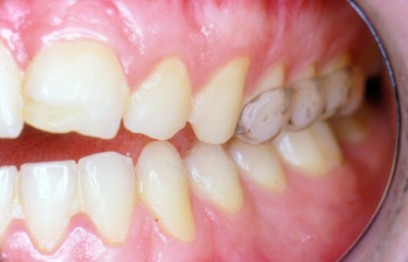

FIGURA 3.- La férula anterior en

visión lateral.

Cubrimos premolares y primer molar

FIGURA 4.- Férula en boca: se

aprecia el levantamiento

de la mordida impidiendo el but a but del

grupo anterior.

Obsérvese la pérdida de esmalte en el incisivo

central

por el contínuo microtraumatismo al

mordisquear.